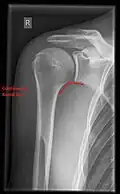

Fracture

Fractures of shoulder bones can include clavicular fractures, scapular fractures, and fractures of the upper humerus.

X-ray

Projectional radiography views of the shoulder include:

- AP-projection 40° posterior oblique after Grashey

The body has to be rotated about 30 to 45 degrees towards the shoulder to be imaged, and the standing or sitting patient lets the arm hang. This method reveals the joint gap and the vertical alignment towards the socket.[26]

-

CR. shoulay film. -

Transaxillary conventional radiography -

Y-projection conventional radiography